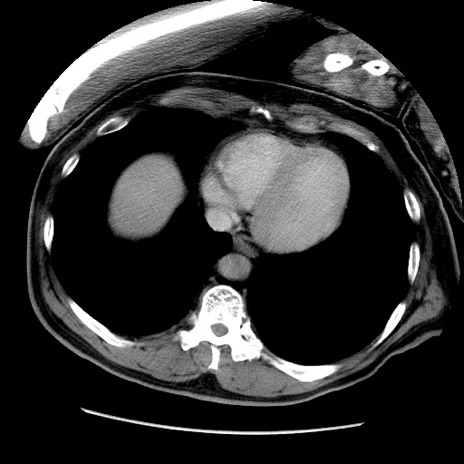

症例22(横断像)

【症例】50歳代男性

【主訴】腹痛

【現病歴】AVMからの被殻出血のため回復期リハ病棟入院中。 本日午後3時頃急に下腹部痛が出現した。

【既往歴】AVM、被殻出血、虫垂炎、高血圧

【身体所見】意識晴明、左半身不全麻痺、会話の理解は良好、36.5°C、腹部:膨隆、全体に板状硬、下腹部正中に圧痛点あり、反跳痛-、筋性防御不明、右下腹部にope scar

【データ】WBC 9400、CRP 0.06